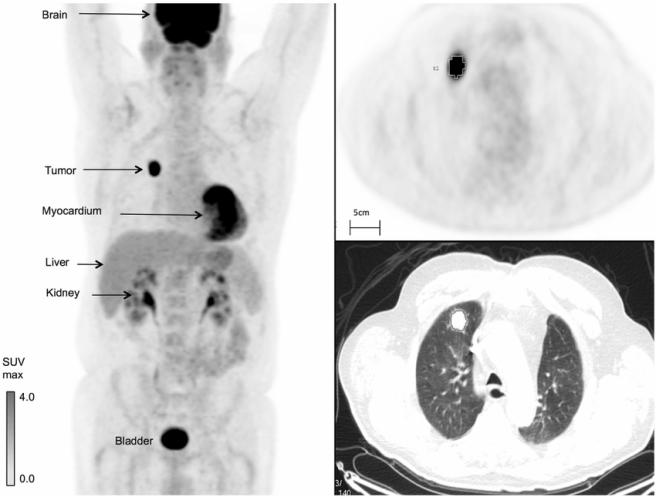

Fluorodeoxyglucose (or FDG) is basically a radiolabelled sugar molecule. It acts in a very similar manner to glucose – being taken up by cells like glucose – and in this fashion it can be used to assess where glucose is being utilised in the body. Such measurements can be used to assess changes in the metabolic activity of the body. For example, given that cancer tumors are high consumers of glucose, FDG is often used to determine where in the body a tumor might be (as in the image below)

FDG imaging of a cancer tumor in the body. Source: Researchgate